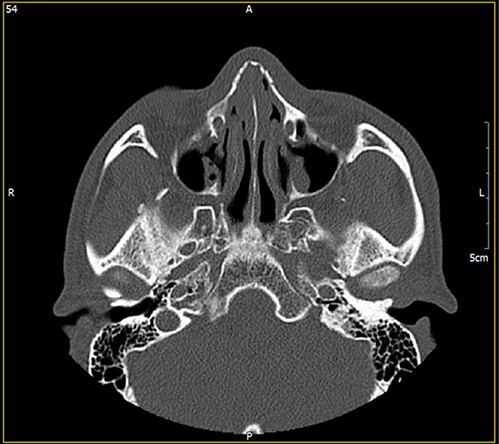

정확한 분석을 위한

체계적 진단골절의 원인을 CT를 통해

정확하고 입체적으로 분석 후

세밀한 상담으로 원인 분석 -